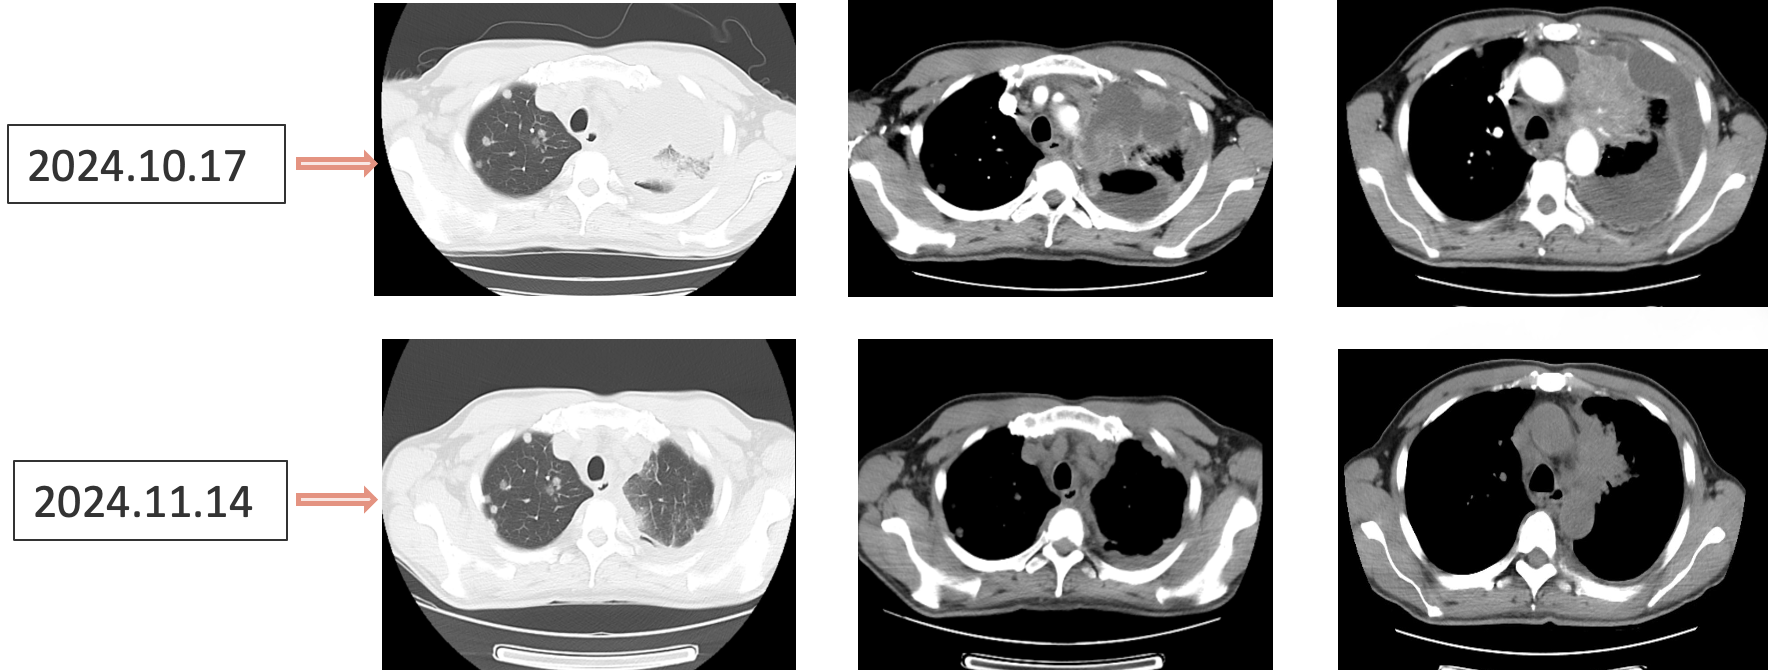

患者采用艾托组合抗体(PD-1/CTLA-4组合抗体)联合卡铂和安罗替尼治疗,同时进行血管内皮抑素胸腔灌注控制胸水。第一周期治疗后出现发热气喘等不良反应,经对症处理后症状改善。6周期治疗后影像学评估显示肺部病灶明显缩小,肝脏及淋巴结转移灶缩小,胸腔积液减少,疗效评价为PR(部分缓解),患者临床症状明显改善,生活质量显著提升。

1. 艾托组合抗体联合方案治疗6周期后,患者肺部病灶明显缩小,肝脏及淋巴结转移灶缩小,胸腔积液减少,疗效评价为PR(部分缓解);

2. 患者临床症状明显改善,胸闷气喘症状缓解,咳嗽减轻,生活质量提高;

治疗结果证实我们的选择是正确的。患者接受艾托组合抗体联合卡铂和安罗替尼治疗后,肿瘤病灶明显缩小,肝脏及淋巴结转移灶缩小,胸腔积液减少,临床获益显著,疗效评价为PR。

姚菲教授:在本例患者的治疗过程中,艾托组合抗体联合化疗和抗血管生成药物治疗对免疫治疗耐药及多线治疗后进展的NSCLC患者显示出良好疗效。患者迅速获得临床缓解,影像学评估显示病灶明显缩小,体现了艾托组合抗体克服PD-1抑制剂耐药的特性,该例患者免疫再治疗挑战成功。